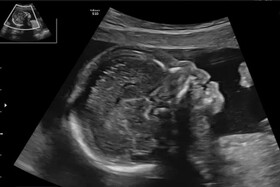

آیا تشخیص زودهنگام «سندرم داون» با شاخص استخوان بینی ممکن است؟

در سالهای اخیر پیشرفتهای تصویربرداری در بارداری به پزشکان امکان داده تا زودتر از گذشته ناهنجاریهای جنینی را تشخیص دهند. یکی از شاخصهایی که در این مسیر اهمیت زیادی یافته، وضعیت استخوان بینی جنین است که میتواند نشانهای از برخی اختلالات ژنتیکی باشد.